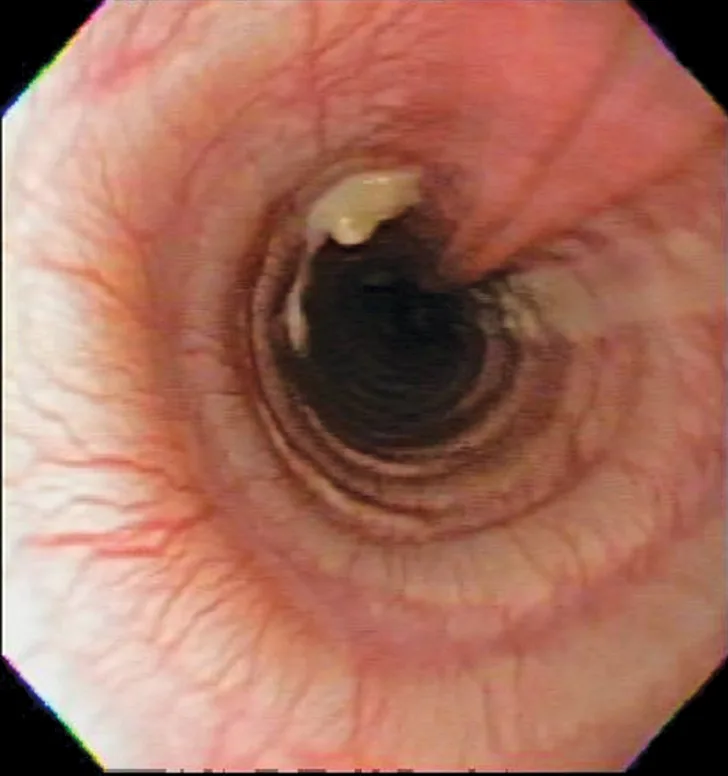

Thoracic radiographs showing a characteristic diffuse, patchy bronchointerstitial pattern (arrows)

Thoracic radiographs revealed a moderate, diffuse, bronchointerstitial pattern (Figure 1). The cardiac silhouette, pulmonary vasculature, and extrathoracic structures were normal. Airway sampling via bronchoscopy was recommended based on radiographic findings. CBC and serum chemistry profile were performed prior to sedation. Serum chemistry results were within normal limits. CBC revealed leukocytosis (24.3 x 103/µL; normal range, 4.9-17.6 x 103/µL) characterized by marked eosinophilia (10.4 x 103/µL; normal range, 0.07-1.49 x 103/µL), monocytosis (1.4 x 103/µL; normal range, 0.13-1.15 x 103/µL), and band neutrophilia (729/µL; normal range, 0-170/µL). Heartworm antigen test was negative.

Thoracic radiographs are generally characterized by a diffuse bronchointerstitial pattern with peribronchial cuffing and thickening of the bronchial walls. In some cases, bronchiectasis or alveolar infiltration may be observed.2,6-8 Occasionally, patchy pulmonary opacities create a nodular appearance.4 Radiography is critical for ruling out other common causes of cough and/or acute respiratory distress. Concurrent disease processes (eg, cardiomegaly, tracheal collapse) can complicate diagnosis.